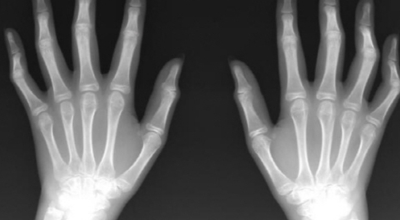

류마티스 관절염은 관절에 만성적인 염증을 유발하는 자가 면역 질환이예요. 자가 면역 질환은 면역 체계가 자신의 인체 조직을 공격할 때 나타나는데요. 일반적으로 류마티스 관절염은 손, 손목, 발에 영향을 미쳐요.

류마티스 관절염 초기증상에서 흔한 증상이예요. 관절을 싸고 있는 활액막에 염증이 발생하며 진행될수록 점차 주변 연골과 뼈로 염증이 퍼지게 되는데 그 결과 온몸의 모든 관절이 쑤시고 저리면서 뻣뻣해지는 것을 시작으로 관절의 통증, 후끈거림, 압통과 함께 부종이 발생해요. 보통 양쪽 관절에 이러한 증상들이 나타나면서 손목, 팔꿈치, 무릎, 손가락, 발가락 같은 관절에 많이 발생한다고 해요.

평상시보다 몸이 부은 것 같은 느낌이 들면 류마티스 관절염을 의심해 볼 수 있습니다. 과도한 염증 반응으로 몸이 부을 수 있으므로 평상시에 잘 맞던 신발이 갑자기 맞지 않거나 손마디가 부었다면 이질환을 의심해볼 필요가 있습니다. 관절 마디가 붓는 이유는 활막이 붓고, 그 주위에 관절 삼출액이라 하는 물이 차기 때문이라고 해요.

이러한 증상이 수개월에서 수년 동안 지속되면 관절의 연골이나 주위 조직이 손상되면서 관절 마디가 휘어지거나 굳어져 마음대로 쓸 수 없게 되는 장애가 생깁니다. 이런 손상을 예방하기 위해서는 초기부터 꾸준하고 적절한 치료를 하는 것이 아주 중요해요.